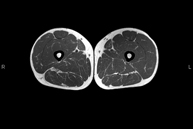

- RM Muslo

Exploración ideal para el estudio de lesiones en músculos isquiotibiales y cuadriceps, frecuentemente lesionados en deportistas. También permite una buena valoración de tendones y nervios periféricos. Tiene una duración aproximada de 20 minutos. No emplea radiación ionizante.